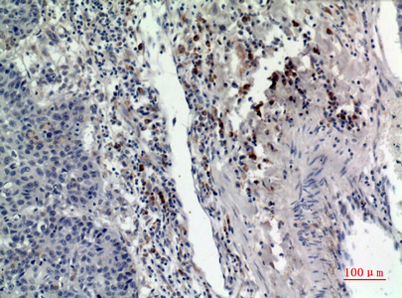

| Dilutions: | Western Blot: 1/500 - 1/2000. IHC-p: 1/100-1/300. ELISA: 1/20000. Not yet tested in other applications. |